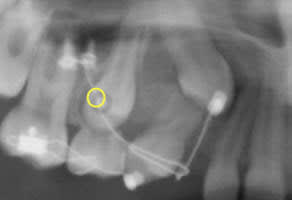

Son émergence du fond du vestibule se situe au niveau du petit cercle que j'ai dessiné sur la radio.